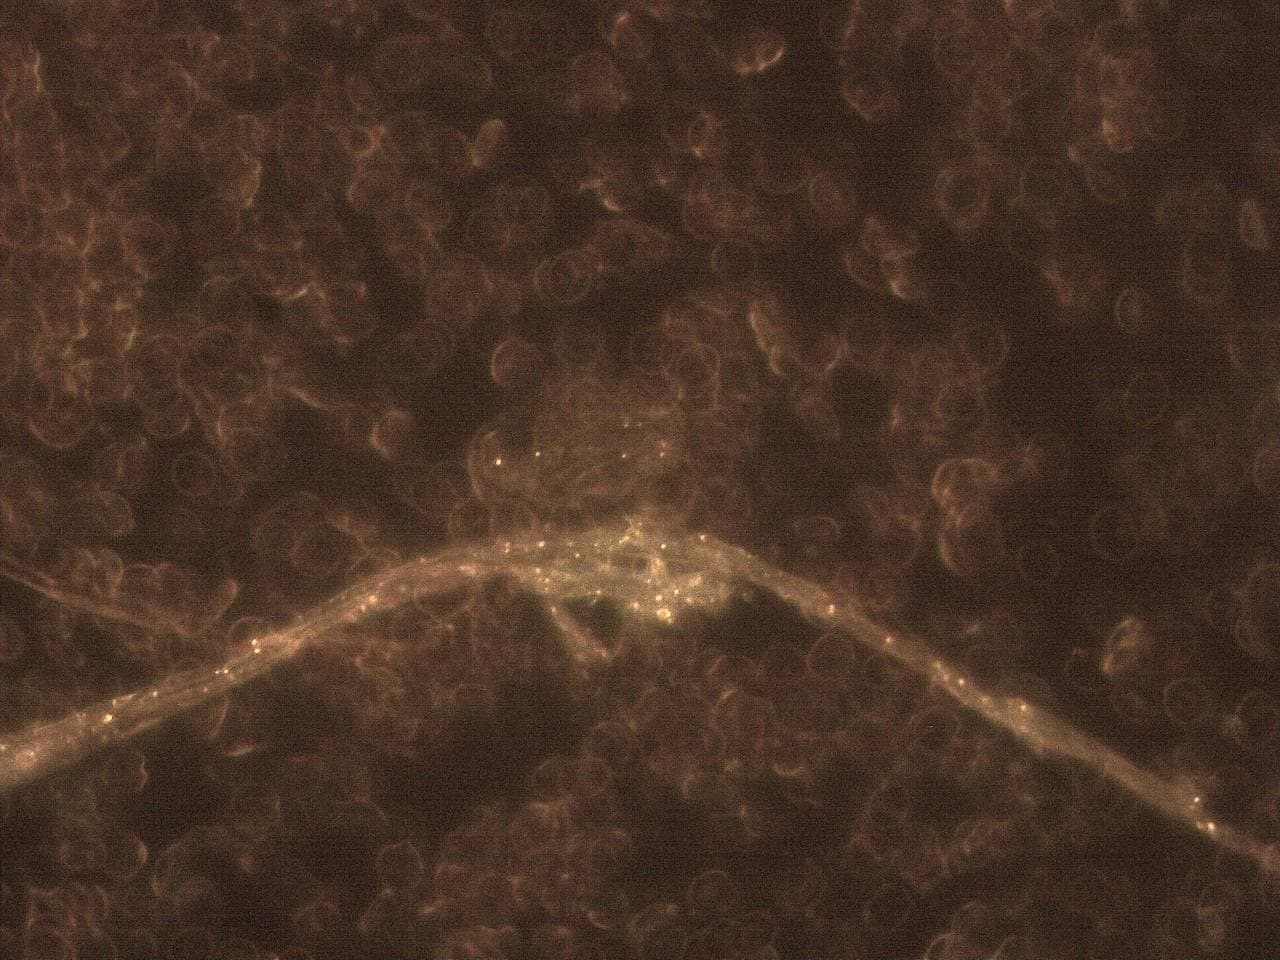

GENimpfschaden

Impfschäden Schweiz Coronaimpfung, [15.09.21

https://t.me/Impfschaden_Corona_Schweiz/21525

Seltsame Form im Blut Erys wirken wie tot

GENimpfschaden im Blutbild 15.9.2021: Foto 4

GENimpfschaden

Impfschäden Schweiz Coronaimpfung, [15.09.21

https://t.me/Impfschaden_Corona_Schweiz/21526

Stechapfelformen

GENimpfschaden im Blutbild 15.9.2021: Foto 5